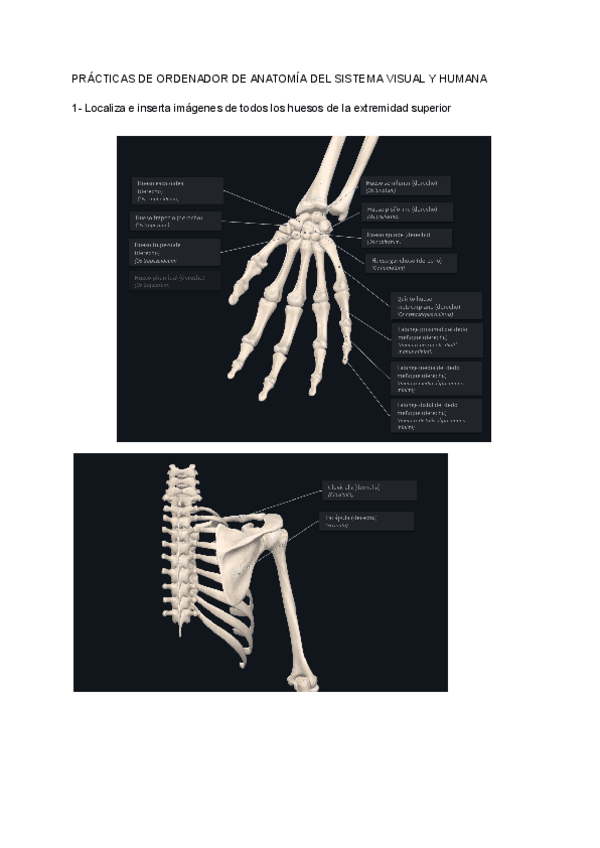

Prácticas

He publicado nuevos practicas de 1º ANATOMÍA DEL SISTEMA VISUAL Y HUMANA: Prácticas